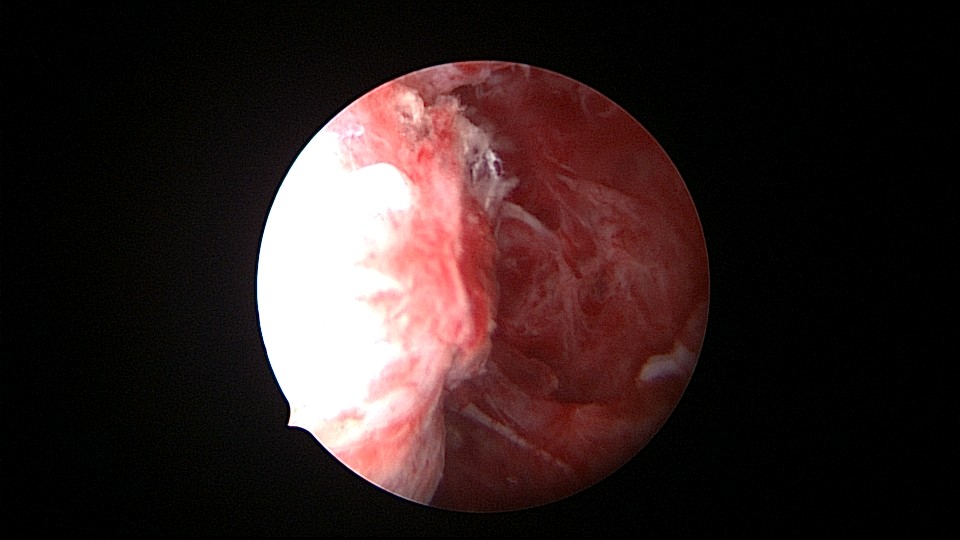

患者55岁,G4P1,顺产1次。安环16年,绝经5年,外院取环失败。子宫前位,宫颈萎缩,宫腔下段左后壁见假道,假道内见肌瘤结节突出,爱母环位置正常,宫腔左侧壁及前壁见占位质脆组织,表面有异常粗大血管。异物钳顺利取出节育环,占位组织病检为内膜样癌。取环造成的假道让病人因祸得福,提前发现了子宫内膜样癌,得以及时手术治疗。